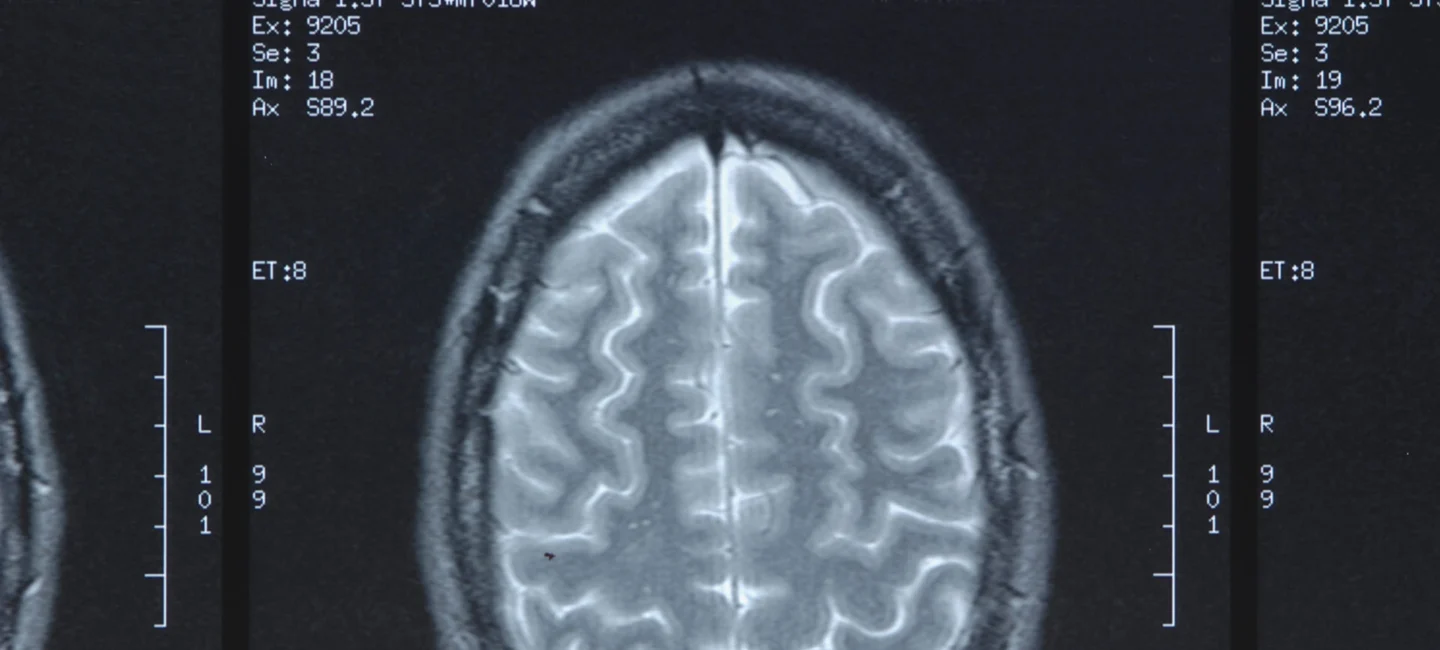

- Hypoxic-ischemic encephalopathy (HIE)

- Infant brain damage